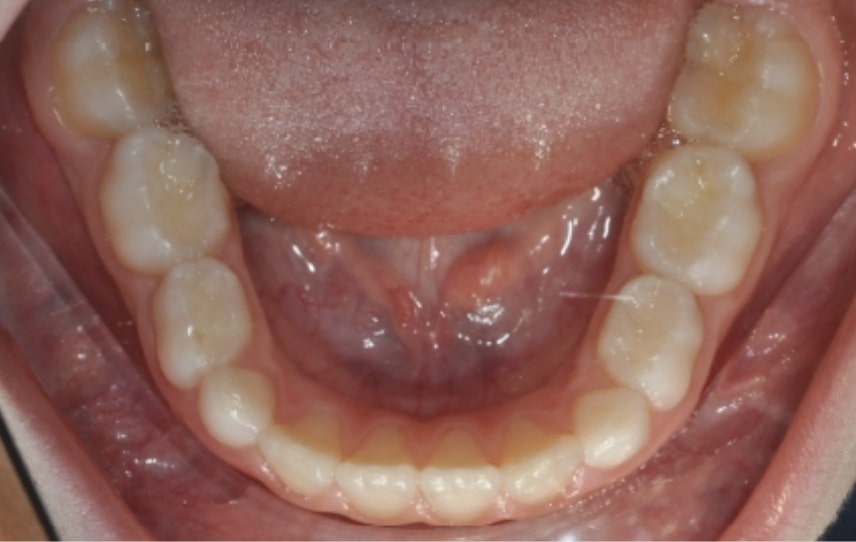

Initial Photos and datas

Clinical examination and diagnosis

DENTAL:

• Deviated Lower Midline 2 mm to the Right